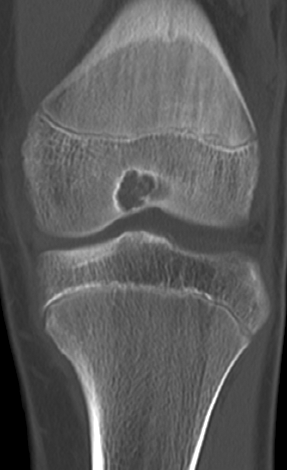

▌地图样破坏

地图样破坏是指肿瘤组织在一个局部呈团块状生长造成界限清楚的骨质破坏(图 1、图 2、图 3、图 4)。病灶可位于骨的中心或一侧部位,呈圆形、卵圆形密度减低区,与正常骨质分界清晰,边缘可有或无硬化带围绕,骨的形态无变化,病灶内可完全透亮或可见粗细不均、大小不等的残留骨嵴,内缘可光滑或呈分叶状压迹。地图样破坏见于大多数良性肿瘤和肿瘤样病变如单纯性骨囊肿、骨纤维结构不良、血管瘤等、也可见于部分恶性骨肿瘤如骨转移瘤、骨髓瘤等。

图 1.地图样破坏:单纯性骨囊肿